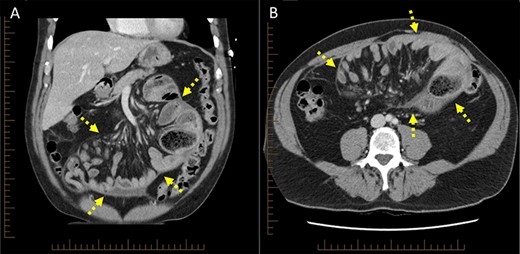

On retrospective review of the case at a multidisciplinary team meeting, the original scans were reviewed and demonstrated central congregation of the small bowel loops encased within a ‘cocoon-like’ thick peritoneal membrane (Fig. 3), characteristic of SEP [3]. A consensus was reached whereby this patient’s presentation was attributed to SEP, otherwise termed ‘abdominal cocoon syndrome’. This diagnosis is exceedingly difficult to make preoperatively, and previous reports have only identified this condition on exploratory laparotomy [4, 5]. Furthermore, given its rare incidence, as well as non-specific clinical and radiological findings, SEP is easily overlooked [6]. This diagnosis was also later confirmed on intestinal ultrasound which demonstrated a centrally clumped ‘cauliflower-like’ appearance of the small bowel, encased within a thickened capsule, depicting a trilaminar sign.

Computed tomography scan (A) coronal cross-section, (B) axial cross-section demonstrating ‘cocoon-like’ membrane enveloping dilated loops of small bowel (arrow).